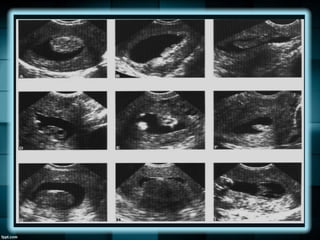

PÓLIPOS ENDOMETRIALES

Se observan en mujeres peri menopáusicas y

postmenopáusicas.

Pueden causar sangrado uterino aunque la

mayoría sin asintomáticos, además de llegar

hasta la infertilidad.

Los pólipos son sobre crecimientos localizados

de tejido endometrial recubiertos por epitelio, y

que contienen un número variable de glándulas,

estroma y vasos sanguíneos.

Pueden ser

pedunculados, o con

una amplia base, o

tener un fino tallo.

Pueden parecer

como un

engrosamiento

endometrial

inespecífico que

puede ser difuso o

localizado.

POLIPOS ENDOMETRIALES

Ocasionalmente se puede ver una arteria

nutriente en el pedículo con el Doppler color.

PÓLIPOS ENDOMETRIALES Se observanen mujeres peri menopáusicas y postmenopáusicas. Pueden causar sangrado uterino aunque la mayoría sin asintomáticos, además de llegar hasta la infertilidad. Los pólipos son sobre crecimientos localizados de tejido endometrial recubiertos por epitelio, y que contienen un número variable de glándulas, estroma y vasos sanguíneos.

PÓLIPOS ENDOMETRIALES Pueden ser pedunculados,o con una amplia base, o tener un fino tallo. Pueden parecer como un engrosamiento endometrial inespecífico que puede ser difuso o localizado.

POLIPOS ENDOMETRIALES Ocasionalmente sepuede ver una arteria nutriente en el pedículo con el Doppler color.